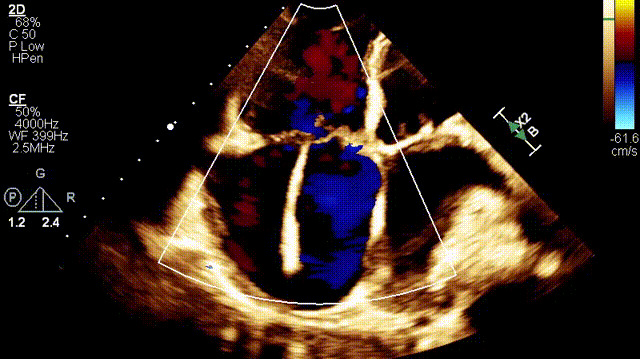

植入前超聲

手術在全麻狀態下開展,此次手術采用經右側頸靜脈入路的方式將輸送器送入患者心臟內,在TEE及DSA引導下調整輸送器頭端角度,使得輸送器與三尖瓣瓣環平面垂直。在輸送器進入右心室后釋放室間隔錨定裝置,而后釋放瓣葉夾持件(2個耳片結構)成垂直狀態。在TEE及DSA確定夾持件固定至三尖瓣葉根部且位于右室側后釋放人工瓣心房側盤片。隨后調整瓣膜同軸性以及室間隔錨定件位置(貼合室間隔),前推藏針管并固定,進而釋放室間隔錨定裝置,并再次確認瓣膜位置、穩定性及同軸性,合攏輸送鞘后撤出輸送器,完成LuX-Valve Plus人工三尖瓣瓣膜的植入。

術后超聲